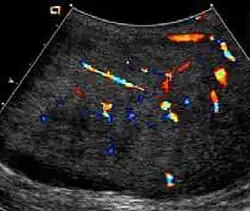

Fig. 10. Epidermoid cyst. Onion peel appearances of the tumor together with absence of vascular flow are typical findings of epidermoid cyst.

Epidermoid cysts, also known as keratocysts, are benign epithelial tumors which usually occur in the second to fourth decades and accounts for only 1–2% of all intratesticular tumors. As these tumors have a benign biological behavior and with no malignant potential, preoperative recognition of this tumor is important as this will lead to testicle preserving surgery (enucleation) rather than unnecessary orchiectomy. Clinically, epidermoid cyst cannot be differentiated from other testicular tumors, typically presenting as a non-tender, palpable, solitary intratesticular mass. Tumor markers such as serum beta-human chorionic gonadotropin and alpha-feto protein are negative. The ultrasound patterns of epidermoid cysts are variable and include:

However, these patterns, except the latter one, may be considered as non-specific as heterogeneous echotexture and shadowing calcification can also be detected in malignant testicular tumors. The onion peel pattern of epidermoid cyst [Fig. 10] correlates well with the pathologic finding of multiple layers of keratin debris produced by the lining of the epidermoid cyst. This sonographic appearance should be considered characteristic of an epidermoid cyst and corresponds to the natural evolution of the cyst. Absence of vascular flow is another important feature that is helpful in differentiation of epidermoid cyst from other solid intratesticular lesions.